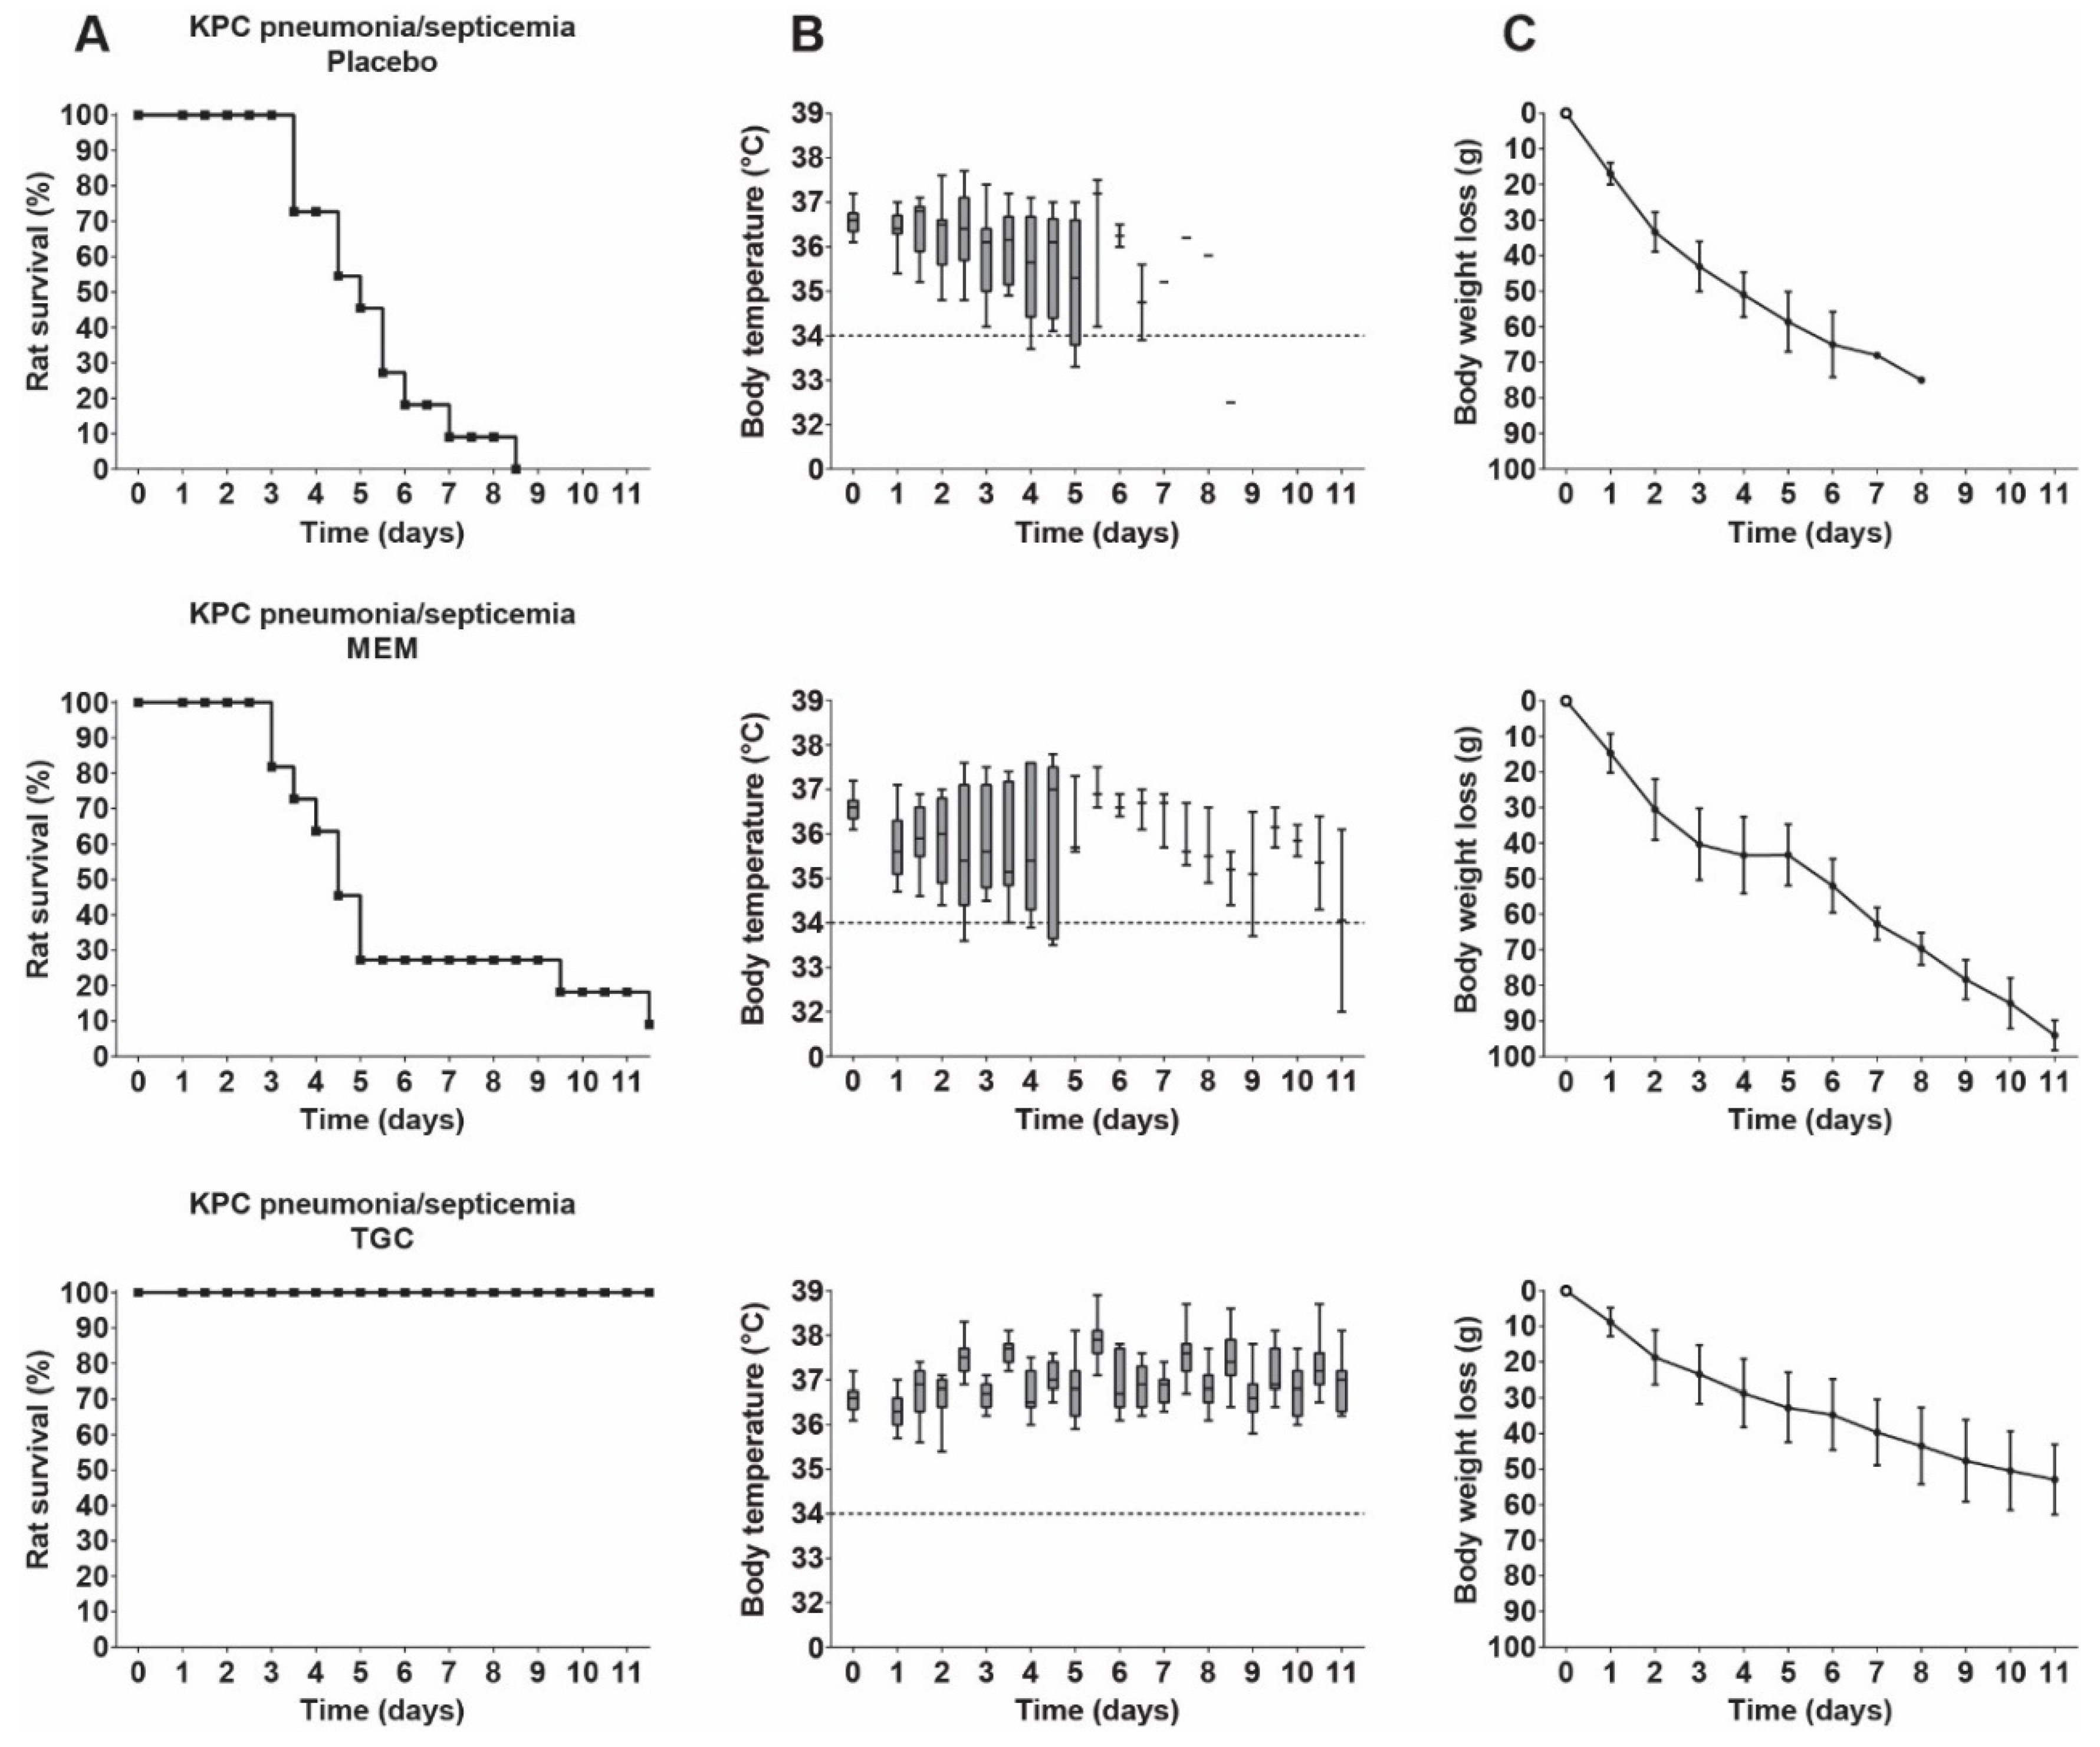

3.7. Therapeutic Efficacy of Meropenem and Tigecycline in Rats with KPC Pneumonia–Septicemia